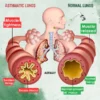

Understanding Lung health

It goes without saying that our lungs are two of the most important organs in our body. They are responsible for providing oxygen for every cell in the human body – meaning that functional lungs are necessary for healthy basic cell functions. The lungs also contract up to 20 times a minute, making them some of the hardest-working organs in the body.

But did you know that some of the most common habits we have can actually destroy our lungs? Here are the common habits that could be damaging your lungs: smoking, poor posture, not exercising, exposure to pollutants, and an unhealthy diet. e. Thankfully, Respira™ Lung Care Spray is developed to naturally support individuals with various lung conditions, providing relief, enhancing respiratory function, and promoting a healthier and happier life.

Respira™ Lung Care Spray offers a potent solution for individuals facing breathing challenges due to conditions such as allergies, asthma, smoking, respiratory illnesses, or a weakened respiratory system. This unique formula is designed to cleanse and strengthen the lungs, alleviate congestion, and promote better breathing, providing relief from a variety of respiratory concerns.